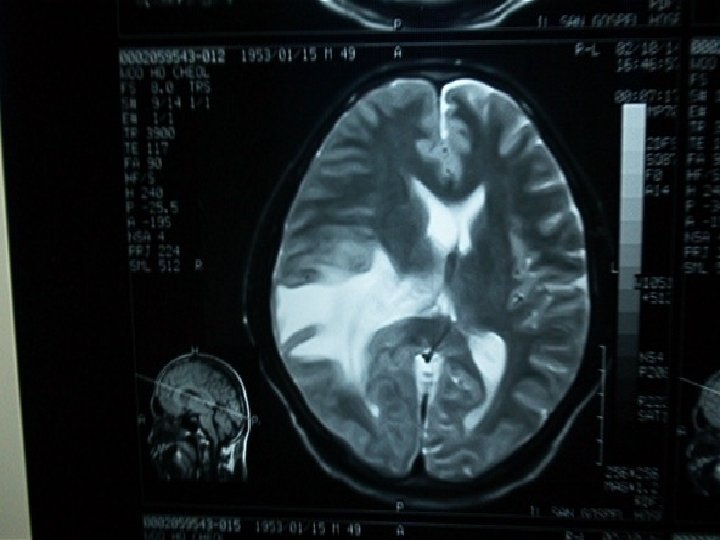

Linfoma SNC

Linfoma SNC

Linfoma SNC

Linfoma SNC